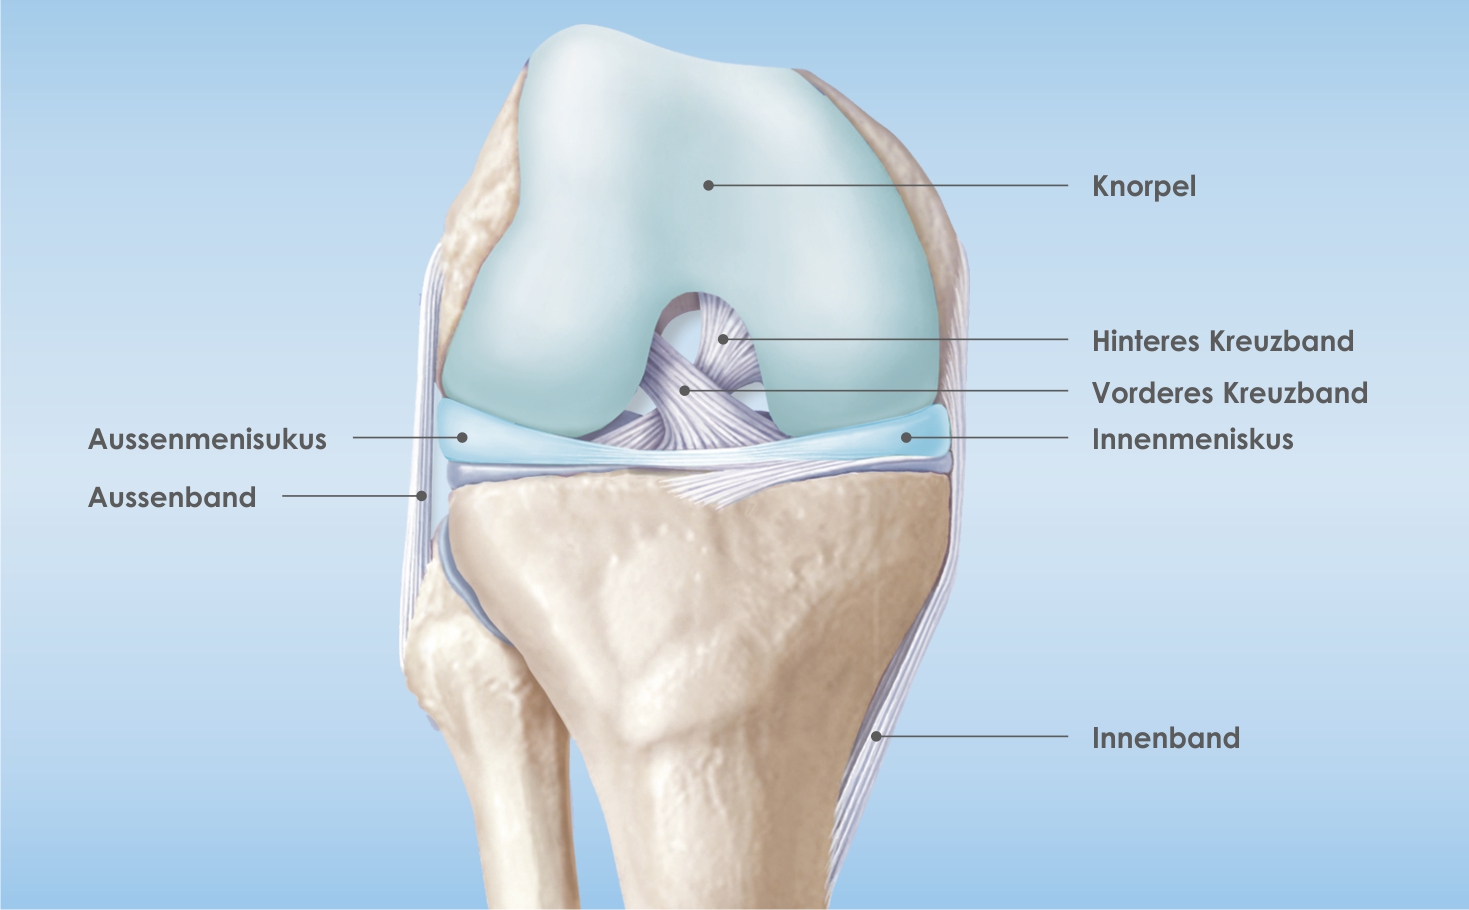

Das vordere Kreuzband verläuft im Kniegelenk von der äusseren Oberschenkelrolle zum Schienbein-Plateau und stabilisiert zusammen mit dem hinteren Kreuzband und den Seitenbändern das Kniegelenk. Durch diese Führung werden andere Strukturen des Kniegelenks wie Menisken und Knorpel vor Zerstörung geschützt.

Rechtes gebeugtes Kniegelenk (ohne Kniescheibe, von vorne)

Die häufigsten Verletzungsmechanismen sind Kombinationen aus Verdreh-, Einknick- und Schubtraumen, die beim Skifahren, Fussballspielen oder bei ähnlichen Sportarten auftreten. Beim Erwachsenen reisst das vordere Kreuzband dabei meist im Verlauf des Bandes selbst, während es beim jungen Patienten auch knöchern ausreissen kann. Als Begleitverletzungen treten nicht selten Meniskus- und/oder Seitenbandverletzungen auf. Auch der Knorpel kann dabei geschädigt werden. Der Patient verspürt beim Unfall meist ein reissendes Gefühl im Knie, diesem folgt bald ein Anschwellen des Gelenks. Oft ist auch ein Geräusch zu hören. Nach einigen Tagen gehen die Schmerzen und die Schwellung zurück, verbleiben kann eine Instabilität am betroffenen Knie.